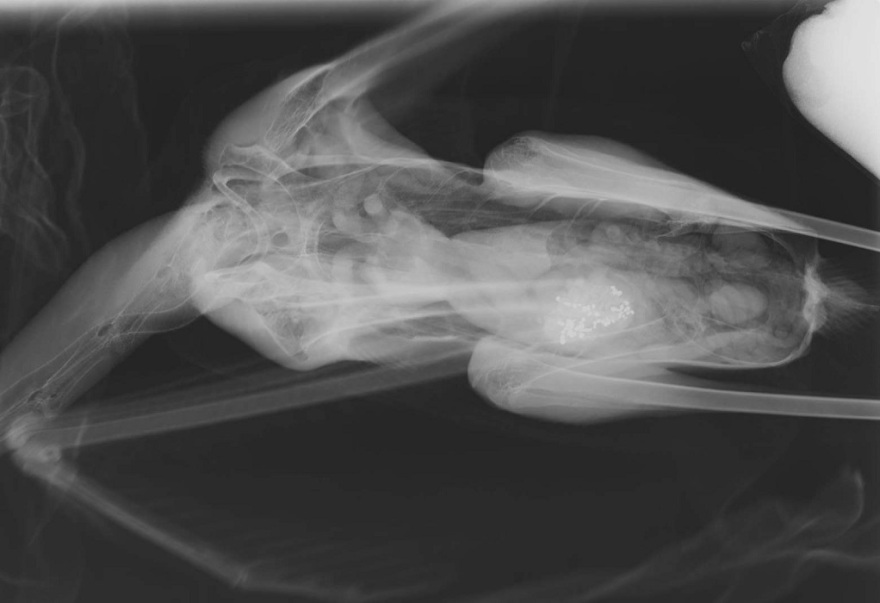

«Όσα έχουν έρθει μέχρι στιγμής, είναι σε προχωρημένη κατάσταση. Επειδή δεν αντέχουν να στέκονται όρθια και μέσα στο νερό δεν μπορούν να καθίσουν, βγαίνουν κάπου στεγνά και ξαπλώνουν. Δυσκολεύονται να κρατήσουν όρθιο ακόμα και το κεφάλι τους. Μέχρι στιγμής, οκτώ πουλιά έχουν έρθει σε εμάς. Κάναμε ακτινογραφίες και επιβεβαιώσαμε ότι στα στομάχια τους υπάρχουν σκάγια μολύβδου. Όταν έχασε το πρώτο τη ζωή του και κάναμε νεκροψία», αναφέρει ο κ. Καλπάκης.